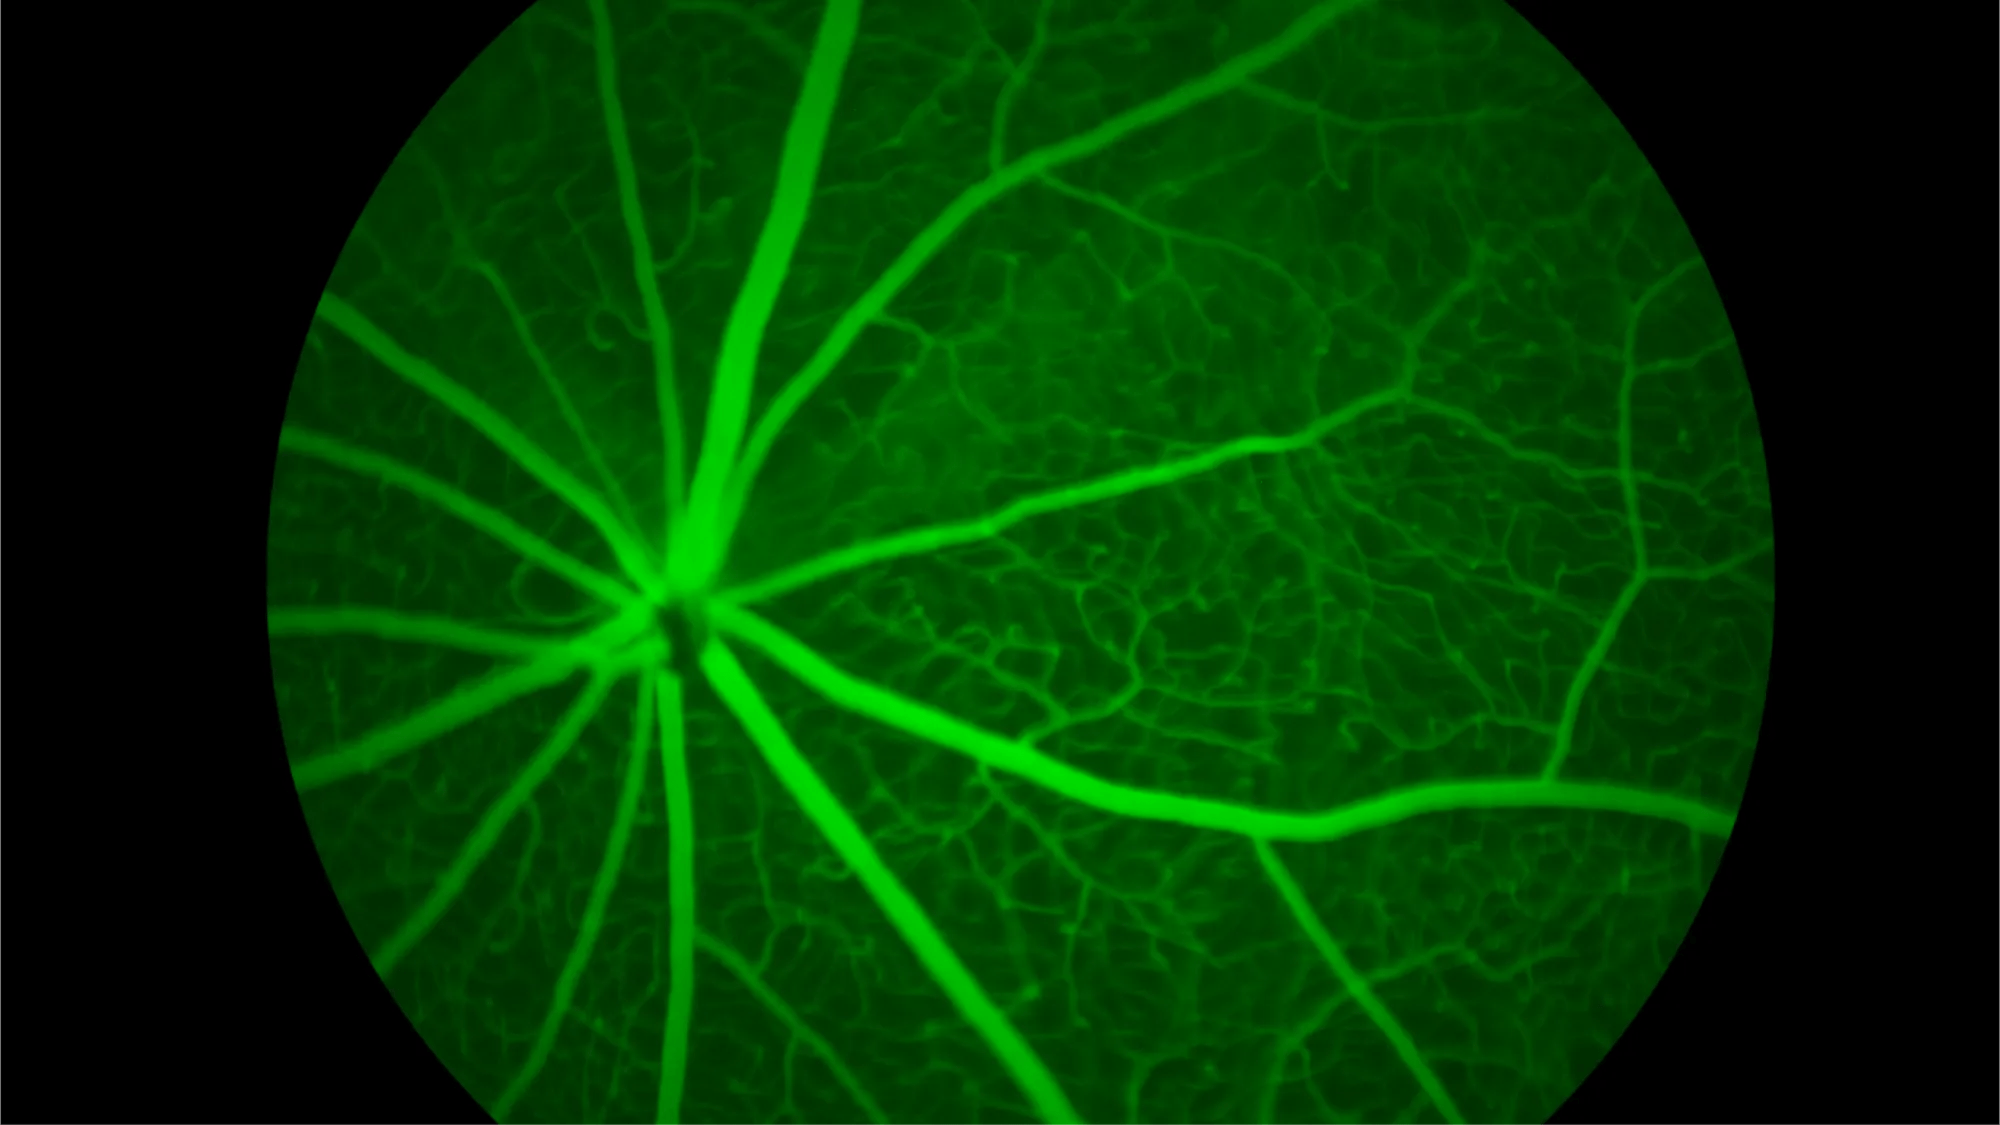

(Bar Harbor, Maine – Feb. 18, 2025) – Vision changes are an inevitable part of aging, but why are some more susceptible to age-related eye diseases and why do some individuals experience more severe decline than others? New research from The Jackson Laboratory (JAX) reveals that genetics play a key role in how the eye ages, with different genetic backgrounds influencing retinal aging in distinct ways.

The study, published in Molecular Neurodegeneration, examined age-related changes in genes and proteins of the retinas of nine strains of mice, mimicking the genetic variability found in humans. While all mice exhibited expected signs of aging, the severity and nature of these changes varied significantly between the nine strains.

In his work, Howell and his team leveraged nine strains of mice with different genetic backgrounds designed to better reflect human variability, generating data on age-related genetic and molecular changes in young and old mice. With their dataset now publicly available, Howell and his team hope their findings will help other scientists studying aging and vision loss – work that may also improve the utility of the eye as a window to the brain to predict neurological decline.

Beyond vision research, this study could have broader implications for neurodegenerative diseases. Since the retina is a direct extension of the brain, understanding how it ages could provide clues about conditions like Alzheimer’s and other forms of dementia.

“The eye is a crucial organ, and this research fills an important gap in our understanding of aging,” said Howell. “But beyond that, the eye is a window into the brain. By understanding how the healthy eye ages, we may be able to work toward new ways of using the eyes to determine people’s risk of developing diseases like Alzheimer’s.”